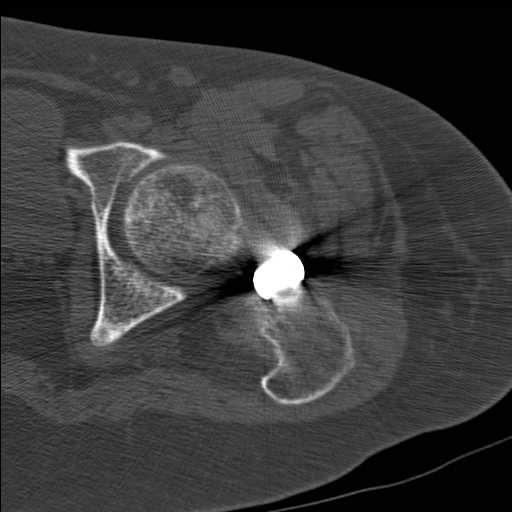

Перелом шейки бедра у девушки 19 лет. Чем лучше помочь?

Добрый день уважаемые коллеги. Во такая ситуация. Девушка 19 лет травму

получила в мае 2016г( изолированная травма, трансцервикальный перелом

шейки левого бедра). Соматически здорова. Лечилась по месту жительства

скелетным вытяжением в течении 1 месяца. Затем переведена в наше

учреждение. 18 июня выполнена операция, детали где , кто и как уточнять

не имеет смысла( из протокола операции: выполнялась передняя артротомия,

репозиция под визуальным контролем) . Учитывая характер выполненного

остеосинтеза, после операции постельный режим 6 недель. Снимки в

хронологии все выкладываю. КТ контроль сделан 2.09.16.  для оценки

состояния  головки бедра. Помогите, определиться с дальнейшей тактикой.